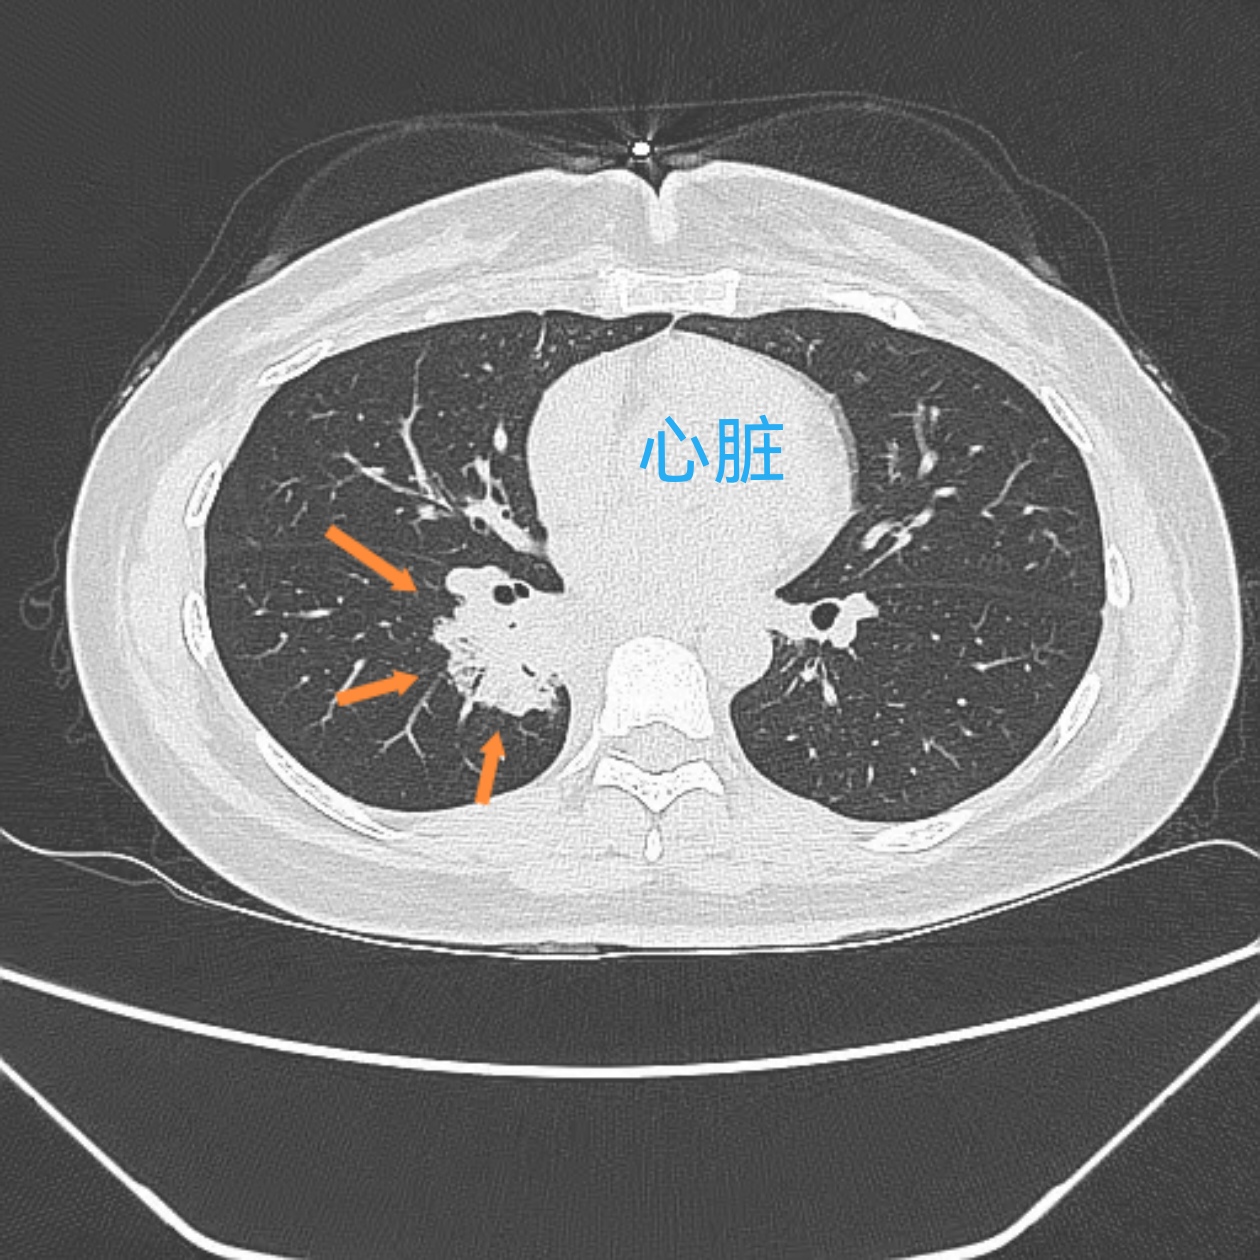

深呼吸胸口疼不一定是肺癌,但肺癌可能引发此症状,其他多种疾病也可能导致类似表现肺癌相关表现肺癌患者可能因肿瘤侵犯胸膜肋骨或神经,在深呼吸或咳嗽时出现胸口疼痛,疼痛常呈持续性或进行性加重此外,肺癌还可能伴随咳嗽咳痰咯血呼吸困难体重下降等症状若怀疑肺癌,需通过胸部影像学检查。

深呼吸胸口痛不一定为肺癌胸膜炎胸腔积液肺炎支气管炎症带状疱疹心绞痛反流性食管炎均可能导致深呼吸时胸口疼痛肺癌可以表现出深呼吸时胸口疼痛,但不能仅凭症状即可诊断肺癌肺癌属于恶性疾病,早期没有症状随着疾病发展,可能出现胸闷胸痛咳嗽咳痰咳血等症状同时可以逐渐加重;吸气时左胸口疼可能由多种原因引起,具体如下胸膜炎或胸膜疾病胸膜是覆盖在肺表面和胸腔内壁的薄膜,当发生炎症如感染自身免疫性疾病等时,吸气时胸膜摩擦加剧,可能引发左胸口疼痛,疼痛常随呼吸动作加重肺部疾病肺炎肺栓塞肺癌等病变可能累及左肺,导致吸气时疼痛例如,肺炎引发的胸膜;2胸膜炎患者会出现深呼吸的时候伴有胸痛,同时还会伴有发热咳嗽咯痰气急等3肺部感染如果波及胸膜,也会出现深呼吸的时候左侧胸口疼痛,常伴有咳嗽咯痰发热甚至伴有呼吸困难等4如果是肺癌的患者,也会出现深呼吸的时候伴有左侧胸口疼痛症状,还会伴有消瘦午后低热咳嗽咯血等5肺;2 胸膜炎胸膜炎症常由感染自身免疫性疾病或肺部疾病如肺炎引发吸气时,炎症刺激胸膜导致疼痛,可能伴随咳嗽呼吸困难等症状治疗需根据病因使用抗生素针对感染消炎药或止痛药,具体方案需医生判断3 肺部疾病肺炎肺栓塞肺癌等疾病可能引起吸气时胸口疼,常伴有发热咳嗽咳痰或呼吸;若支气管镜检查发现支气管内存在异常肿物,且通过夹取组织进行病理学检查明确存在癌细胞,则可确诊为肺癌此时,吸气时胸口疼痛及肺结节均为肺癌的直接表现肺癌导致的胸口疼痛通常与肿瘤侵犯胸膜肋骨或神经有关,而肺结节则是肿瘤在肺部的局部表现若支气管镜检查未发现异常肿物,则吸气时胸口疼痛及肺。

肺肿瘤肺肿瘤,尤其是恶性肿瘤,也可能导致胸口疼痛肺癌患者还可能伴有咳嗽咳痰咯血体重下降等症状如果胸片或肺CT出现肿块影,并经过进一步检查确诊为肺恶性肿瘤,应根据病情考虑手术治疗放疗化疗等综上所述,当患者出现左胸口深呼吸隐隐作痛时,应及时就医,完善相关检查,以明确诊断并;深呼吸胸口疼不一定是肺癌,也有可能是其他的肺部疾病,比如胸膜炎胸腔积液肺和支气管炎症等等其他的心绞痛或者反流性食管炎,也有可能造成深呼吸胸口疼,不能凭这个症状诊断肺癌如果是肺癌,也有可能有这个症状,肺癌属于呼吸系统的一种恶性肿瘤,肺癌可能早期没有明显症状,但是随着病情发展会表现;深呼吸胸口疼不一定是肺癌胸壁疾病是常见原因之一,例如肋软骨炎肋间神经炎或胸膜炎这类疾病会因胸部肌肉骨骼或神经受刺激而引发疼痛,尤其在深呼吸咳嗽或体位改变时加重肺部疾病中,肺炎肺结核及肺癌均可能引起胸口疼痛肺炎和肺结核通过感染导致肺部炎症,刺激周围组织肺癌则可能因肿瘤压;3心脏疾病虽然深呼吸时胸痛不一定源于心脏,但心肌梗死心肌缺血坏死或心绞痛冠状动脉狭窄导致心肌供血不足可能表现为胸痛,且可能因呼吸动作加重心肌梗死疼痛通常剧烈,伴压迫感心绞痛多在劳累或情绪激动时发作,休息后缓解4肋骨或胸部损伤肋骨骨折胸骨骨折或胸部挫伤会直接损伤骨或软组织。